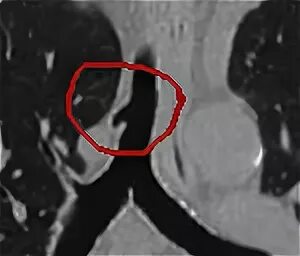

Дивертикул трахеи